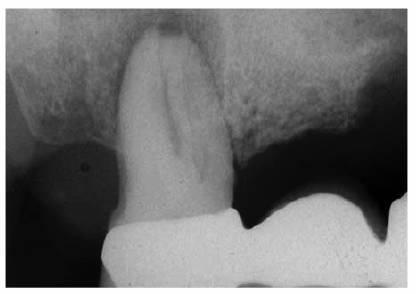

angulations of the suspected tooth (Figures 19-24A

and B).

Figure 19-24A and B: (A) Pretreatment radiograph of a mandibular premolar shows one canal. (B) A second radiograph taken from an angulation of 15 degrees from the mesial discloses a second root.